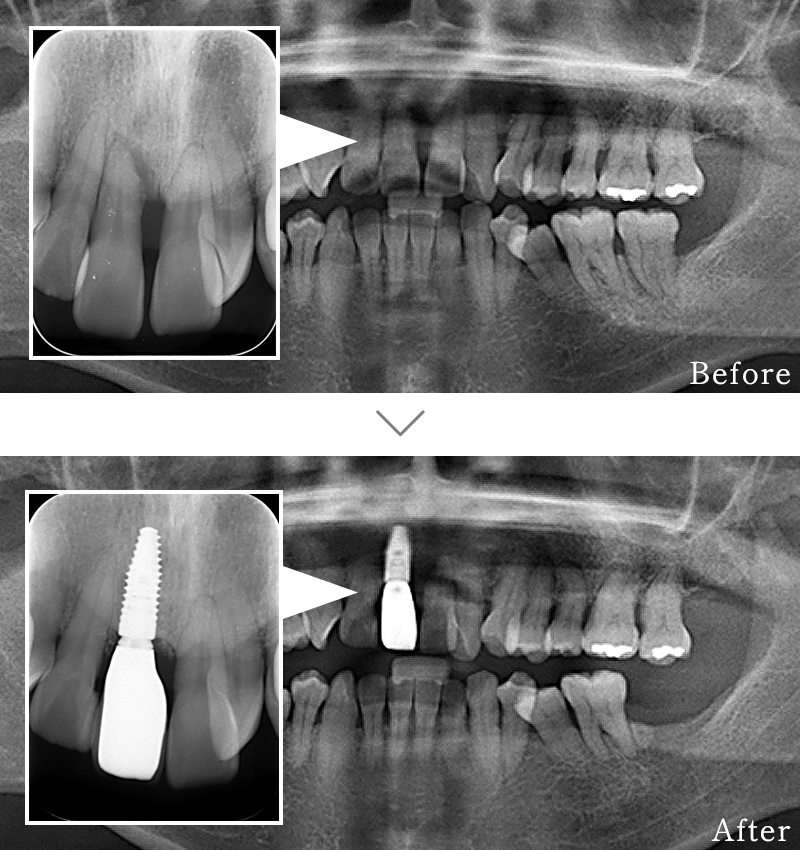

CASE5

主訴 前歯がグラグラして噛めないのと抜けそうで心配。

治療法 抜歯した後、歯周病で溶けて無くなってしまった骨を再生する手術とインプラント手術を同時に行なっています。

治療期間 8ヶ月

費用 CT:16,500円(税込)

+ インプラント治療:525,800円(税込)

+ 造骨処置:88,000円(税込)

合計:630,300円(税込)